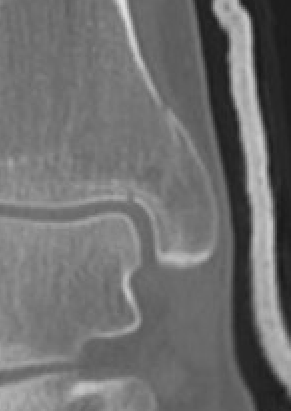

![]() |